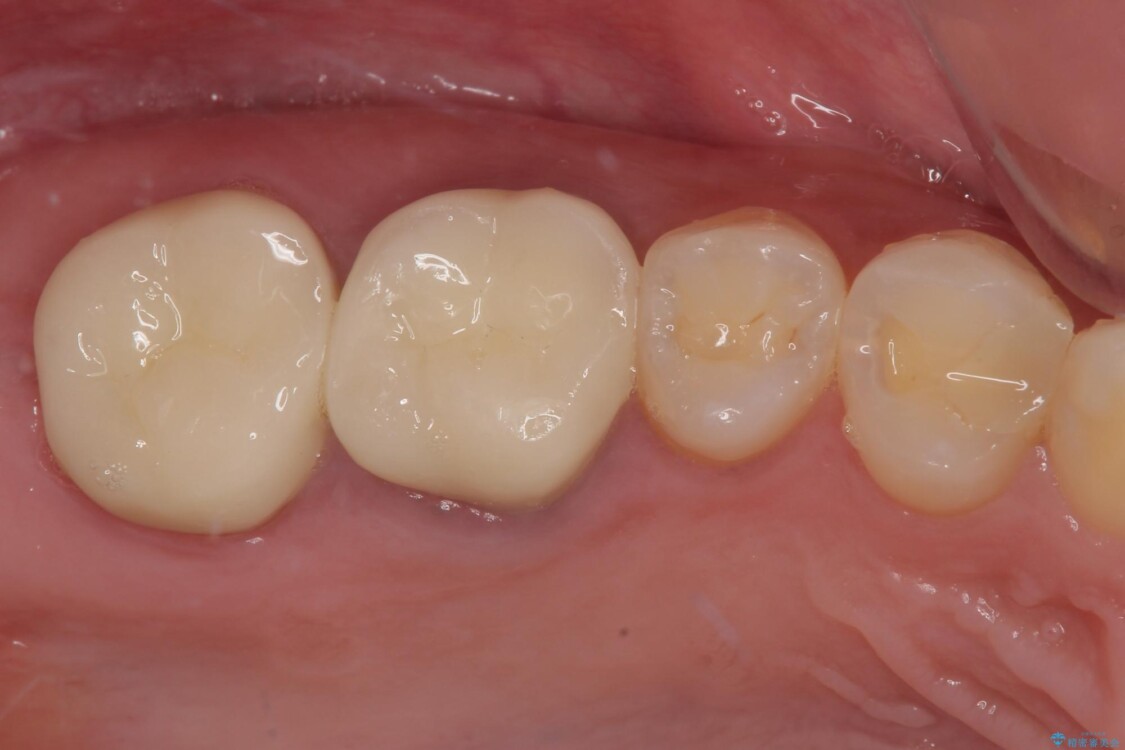

その後、挺出していた右上第一大臼歯と第二大臼歯に装着されていた銀歯についても、審美性と適合性の向上を目的に、オールセラミッククラウンにやり替えました。

これにより、より自然で美しい見た目と、高い精度の咬合が得られています。

治療後

• 挺出歯を圧下してスペースを確保!目立たない部分矯正で下顎大臼歯にインプラント治療を実現 治療後画像